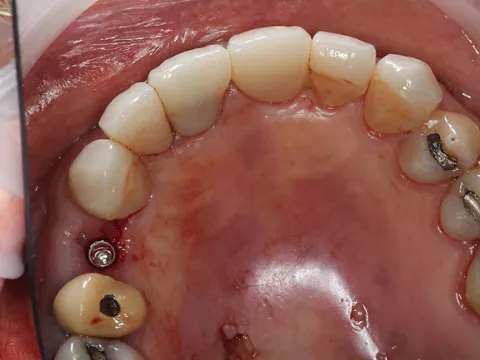

7. Distal implant placed with a cover screw, and mesial implant restored with a HealFit® SH anatomical healing abutment.

7

Suturing was adapted to each implant site. The distal implant was fully submerged with a cover screw, requiring complete primary closure. At the mesial implant, where a HealFit® SH abutment was placed, only two simple interrupted sutures were placed mesially and distally to stabilize the soft tissues.

8. Suturing was adapted to each implant site. The distal implant was fully submerged with a cover screw, requiring complete primary closure. At the mesial implant, where a HealFit® SH abutment was placed, only two simple interrupted sutures were placed mesially and distally to stabilize the soft tissues.

8

Three months after implant placement, a second‑stage surgery was performed at the distal site to uncover the implant following successful osseointegration. A standard healing abutment was placed, as this implant had initially been placed subcrestally with a cover screw due to insufficient primary stability and required conventional freehand placement.

In contrast, the mesial implant had achieved adequate primary stability at surgery, allowing the use of a HealFit® SH anatomical healing abutment from the time of placement. This resulted in progressive transmucosal shaping without the need for additional surgical intervention. At re‑evaluation (8.), peri‑implant soft‑tissue maturation was already complete at this site, illustrating the clinical advantages of immediate transmucosal conditioning, including reduced need for second‑stage surgery, minimised soft‑tissue trauma, improved emergence profile development, and a more streamlined prosthetic workflow.